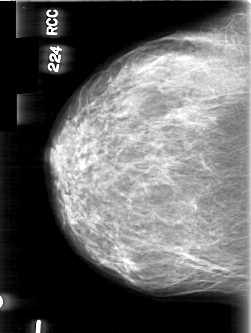

D_4061_1.RIGHT_CC

RIGHT_CC LINES 4981 PIXELS_PER_LINE 3751 BITS_PER_PIXEL 12 RESOLUTION 43.5 NON_OVERLAY